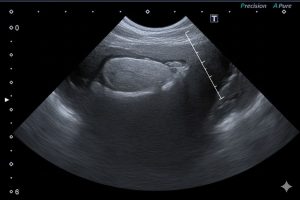

- 血液検査・エコー検査を即日実施

- 副腎腫瘍の早期発見に注力

▶ 13歳・柴犬(副腎腫瘍)

エコー検査により副腎腫瘍を発見。専門施設へ手術紹介。